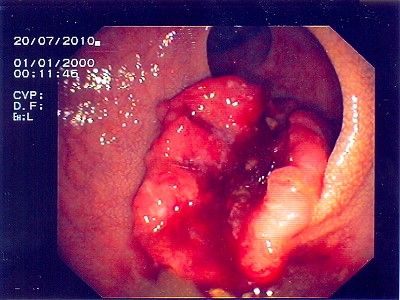

Abb. 3: Hier liegt das bösartige Gebilde exakt im Bereich des Überganges von Dick- zu Dünndarm. Die Umrisse des Überganges (bauhin'sche Klappe) kann man noch erkennen. Abb. 3: Hier liegt das bösartige Gebilde exakt im Bereich des Überganges von Dick- zu Dünndarm. Die Umrisse des Überganges (bauhin'sche Klappe) kann man noch erkennen.